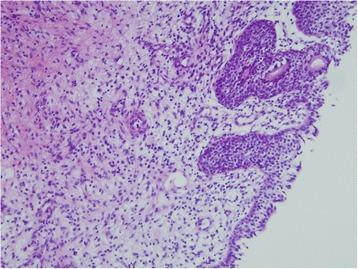

A 9-year-old Mongolian girl was referred to our hospital with a 2-week history of frequent adherence of a small amount of blood to her underwear. We found a sessile smooth margin, a clear boundary and an elastic, soft red tumor over the entire circumference of the urethral meatus. At the beginning, because of the child's age, urethral prolapse was suspected. There was no response after 3 weeks of conservative treatment with steroid ointment. With the patient under general anesthesia, a partial tumor resection was performed for the purpose of histological examination. The tumor excision was limited to about 1/2 laps of the urethral meatus to prevent the development of urethral stricture. On the basis of clinical and histopathological examinations, a diagnosis of a urethral caruncle was made. Post-operatively, steroid ointment application to residual masses was continued, and these disappeared about 6 months later. Our patient was free of recurrence and had had no complications after 3 years of follow-up.

一名9岁蒙古族女孩因内裤上频繁少量沾血2周被转诊至我院。我们在尿道口整个圆周上发现一个有蒂、边缘光滑、边界清晰且质地柔软、有弹性的红色肿物。起初,由于患儿年龄,怀疑为尿道脱垂。使用类固醇软膏保守治疗3周后无反应。在全身麻醉下,为进行组织学检查对肿物进行了部分切除。肿瘤切除范围限于尿道口约1/2圈,以防止尿道狭窄的发生。根据临床和组织病理学检查,诊断为尿道肉阜。术后,继续对残留肿物涂抹类固醇软膏,约6个月后肿物消失。我们的患者在随访3年中无复发且无并发症。